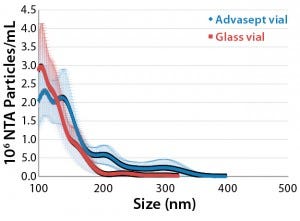

NTA Analysis: As Table 3 shows, we observed slightly larger aggregates in the Advasept vials than in glass. However, the total number of particles are statistically comparable for both container–closure systems (Figures 5–7).

Figure 5: Mean submicron particle-count

data (nanoparticle tracking analysis) for MAb

formulations stored in glass and Advasept vials

for 12 months at 5 °C